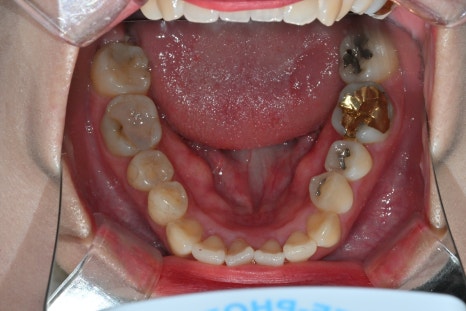

This patient was a 27-year-old woman who visited us because of aesthetic issues with an upper front tooth crown treated about 10 years ago.

A black line visible at the gums

A color difference from the surrounding teeth

An unnatural look in the front teeth

As time passes, upper front tooth crowns can look different from the original result as the gums recede or the internal structure changes. In such cases, rather than simple maintenance, it is necessary to improve them naturally through retreatment.

In this case as well, after removing the existing prosthesis and core,

a stable structure was recreated with a resin core.

This process is

a key step that determines the stability and natural appearance of the result.